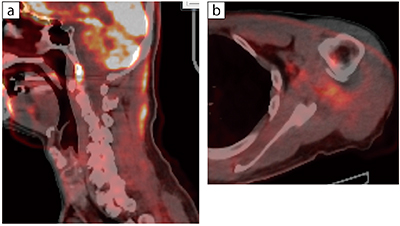

図3 頸部・肩関節の炎症

a:頸部炎症 b:左肩関節周囲炎

がんの再発チェックでPET-CTを実施。画質が向上したことで、再発の確認だけでなくアクティブな炎症(痛みの部位)を発見でき、実際に治療までつなげている。本症例は、MRIではアクティブな炎症であるかまでは判断できなかった。PET-CTの整形領域への貢献の可能性も感じられる。